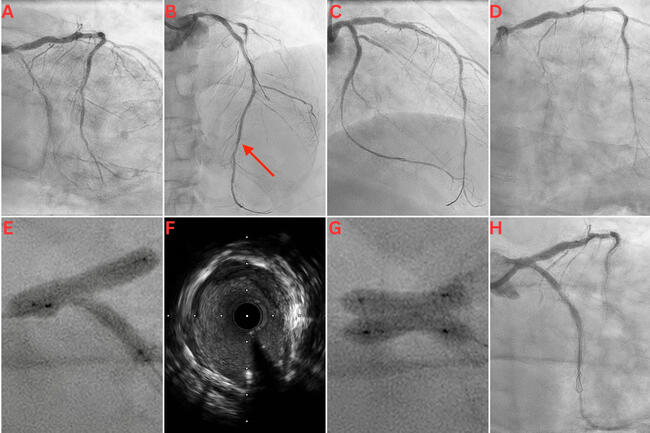

Video 2. The final angiogram following intravascular ultrasound-guided percutaneous coronary intervention of the left main coronary artery (LMCA), left anterior descending artery, and left circumflex artery, with extensive calcium modification, including kissing balloon inflation with 2 OPN NC balloons (SIS Medical AG) in the LMCA.